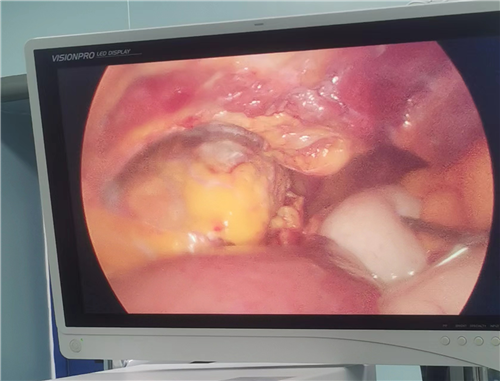

面对这一生命危在旦夕的紧急状况,科主任张秋成迅速集结治疗团队,综合评估患者病情,决定紧急施行“腹腔镜探查+膈肌修补”手术,备选中转开腹方案,确保万无一失。在详尽告知患者及其家属手术风险及可能并发症后,获得全力配合。手术中,团队发现左侧膈肌、心包及胸膜腔破裂,胃与大网膜疝入胸腔,左肺完全压缩。经过精细操作,成功将疝入器官复位,修复破裂部位,手术出血量极少,患者生命体征平稳,顺利返回病房。